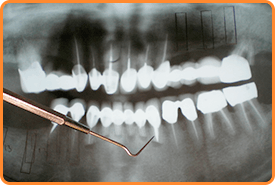

レントゲン検査

レントゲン撮影によって骨の密度を確認し、歯周病の進行度を調べます。

骨密度が低いほど歯周病が進行しています。